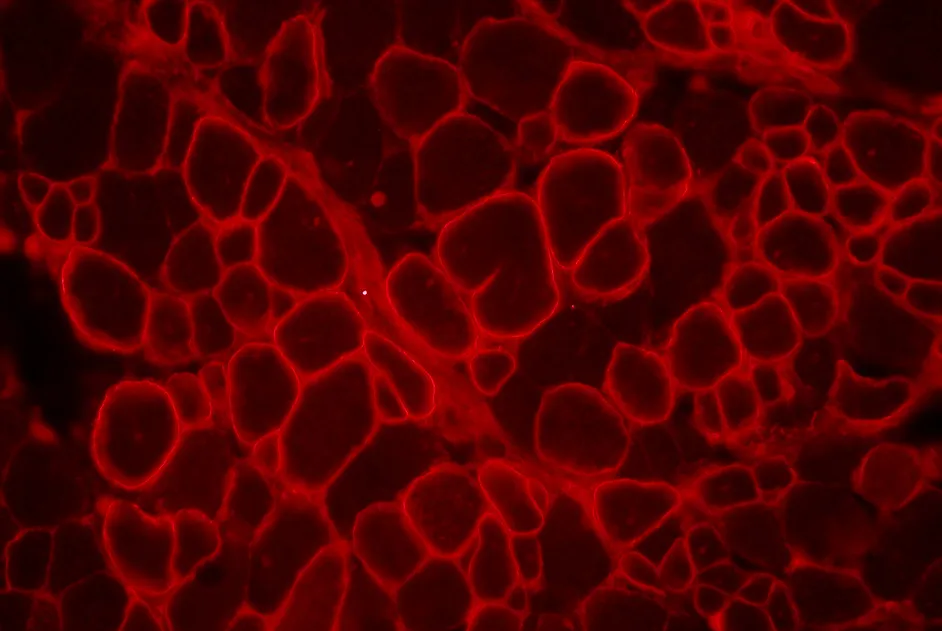

Premières études sur des fœtus FSH mettant en évidence l’expression de gènes impliqués dans la maladie dès ce stade précoce du développement.